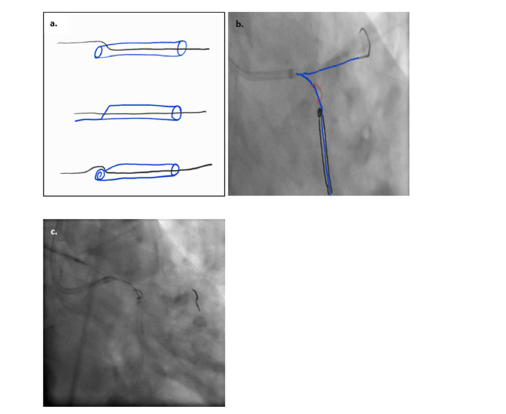

A Sion guidewire was then steered across the LCX stent with Corsair support, and predilation was performed using a 3.5×15mm Sapphire II NC balloon; however, a subsequent IVUS pass demonstrated the wire had passed behind the stent struts across a crushed proximal segment. The team elected to completely crush the compromised stent and stent across from the LM into the LCX. Still, even a low-profile 1.5mm balloon could not be advanced, and a GuideLiner could not be delivered alongside the LAD wire within the 6 F guiding catheter. While attempting to advance the Corsair, the microcatheter adhered to the LCX wire, and LCX access was lost. High-magnification fluoroscopy and IVUS then revealed a spiraling collapse of the proximal LCX stent struts-consistent with a rare geometric configuration we term the Swiss Roll Effect (see (Figure 1) for the fluoroscopic/IVUS appearances, and (Figure 2) for representative IVUS frames). Access was upsized to a 7F femoral approach. A Sion Black wire, supported by a Turnpike LP microcatheter and a GuideLiner, was advanced by tracking along the trapped wire within the rolled, crushed proximal LCX segment and into the distal LCX stent lumen, as confirmed by IVUS. The Sion Black was exchanged for a Grand Slam wire to improve support.

Figure 1:Diagrammatic representation of the swiss roll effect. (a) Schematic showing partial stent compression followed by repetitive manipulation (such as IVUS catheter passage) across the crushed segment. (b, c) Progressive crimping of the compressed stent into its ostium results in spiraling inward collapse, luminal obstruction, and impaired blood flow. The digital arrows highlight the site of inward folding and occlusion.